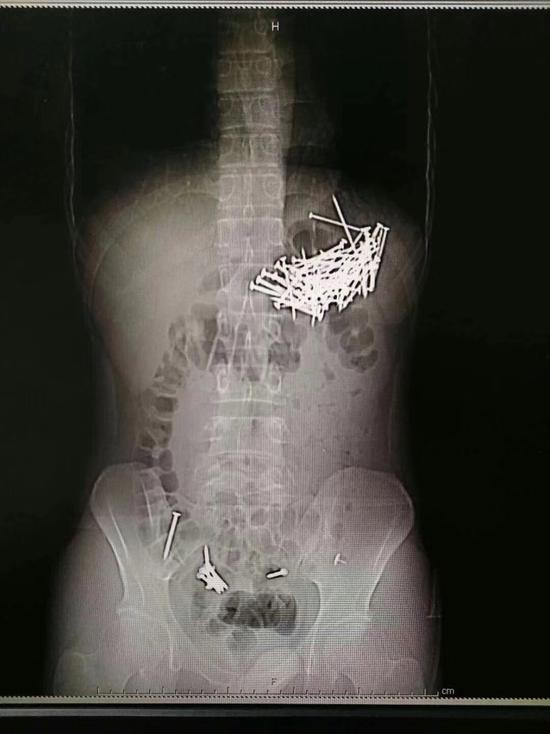

小伙子体内被发现大量钉子 医院供图

8月8日晚上,医院接到求救信息,一个在北湖路某酒店居住的小伙子称自己吃了包子后肚子疼痛难忍,需要医生急救。120急救人员将其接到医院后发现,小伙子所吃的包子馅有异常。“拍片之后可以看到,他的肚子内有大量钉子状物体。”郴州市第一人民医院一名值班医护人员表示,在手术之前,小伙子交给医生一封写给女友的“遗书”,说是若找不到亲属,可以打电话给女友。

据手术医生介绍,经过检查和手术证实,这个小伙子吞食了87根铁钉和7枚图钉,其中6枚图钉被病人自行排出,目前余下一枚图钉在直肠附近,由于体积较小,病人应该可以自行排出。